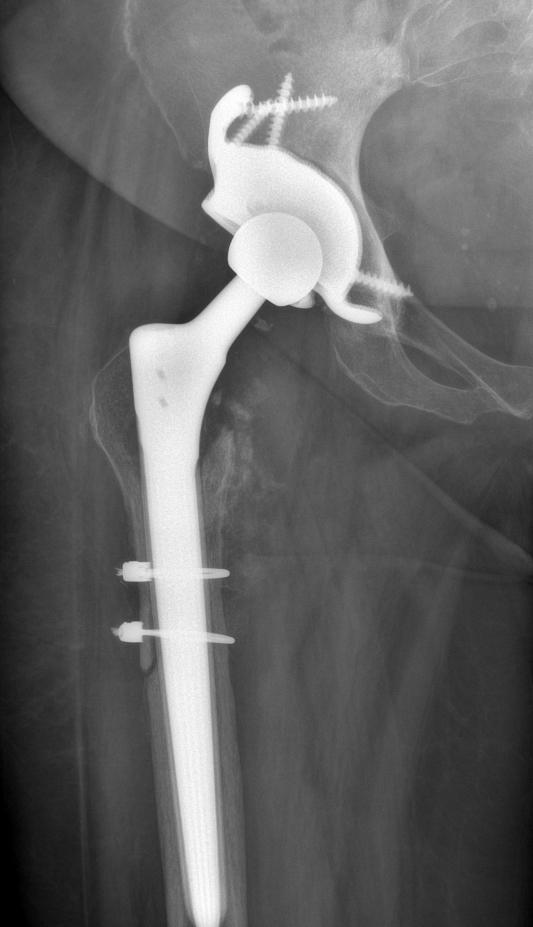

Joint Replacement

Revision Joint Replacement